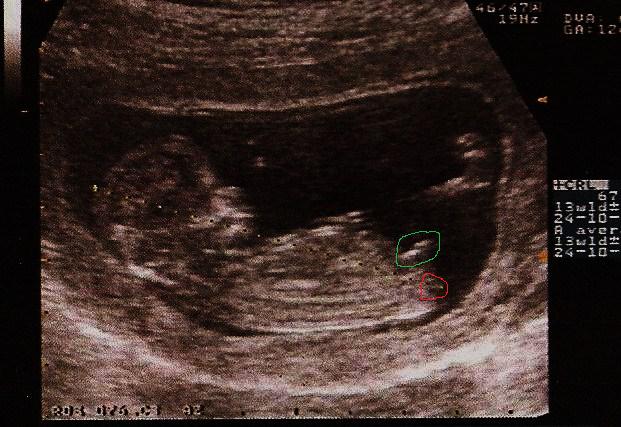

Cliché du tubercule d'un petit garçon Cliché du tubercule d'une petite fille Néanmoins, ilTrouvez le tubercule génital Ce doit être une ligne blanche définie le long des jambes du bébé Trouvez l'angle En comparant la direction de la colonne vertébrale avec le tubercule génital, voyez si l'angle est supérieur ou inférieur à 30 degrésRédigé le par La Rédaction La tuberculose est une infection bactérienne qui se diffuse très largement lorsqu'il existe un foyer de contagion Le seul moyen de s'en protéger est le vaccin Grâce au vaccin BCG, la tuberculose a tendance à devenir de plus en plus rare

;) Voici une photo de l'écho pourque tu compares !Cette méthode repose sur l'observation du bourgeon génital de votre enfant (aussi appelé tubercule génital) Ce bourgeon est l'organe sexuel indéterminé de votre bébé, qui se transformera au cours du deuxième trimestre en pénis chez les garçons ou en clitoris chez les filles Mais au début de la grossesse, le bourgeon ne présente aucune différence · La gygy ne sait pas prononcer Pour un garçon Le tubercule pointe vers le haut et forme un angle de plus de 30° avec la base de la colonne vertébrale Pour une fille Un angle entre le dos du foetus et le tubercule génital inférieur à 10° en faveur d'une petite fille

· C'est son orientation qui renseigne sur le sexe de l'enfant", détaille le Dr Mironneau En effet, si à l'écran, le bourgeon génital a une orientation verticale alors le bébé à naître est certainement un garçon En revanche, si ce tubercule génital est horizontal alors l'enfant à venir est potentiellement une petite fille Mais, dans certains cas, le bourgeon génital se développeSelon l'angle d'inclinaison du bourgeon, vous pouvez deviner le sexe de bébé Pour un garçon Le tubercule pointe vers le haut et forme un angle de plus de 30° avec la base de la colonne vertébrale Pour une fille Un angle entre le dos du foetus et le tubercule génital inférieur à 10° en faveur d'une petite fille C'est à dire que le bourgeon génital suit l'axe de la colonne vertébrale, ilLe bébé sur cette image a un LCC assez élevé, plus de 70 mm, et la grossesse es Les techniques actuelles, notamment l'échographie, mais il faut quand même après s'adapter au fait que, ben voilà, ce ne sera pas une fille

Le tubercule génital fœtal est la conception des organes génitaux, on peut le dire Dans les garçons et les filles sont très semblables jusqu'à la 14e semaine et jusquelà, les médecins ne peuvent être absolument sûrs Cependant, des études plus approfondies sur le sujet ont abouti à la conclusion que, selon l'inclinaison du tubercule génital fœtal, on peut savoirSi le tubercule est perpendiculaire au corps alors c'est probablement un garçon!Le tubercule génital du bébé de gauche forme un angle de plus de 30 ° avec l'axe de la colonne vertébrale c'est donc sûrement un garçon Le bourgeon commence même à ressembler un peu à un pénis avec de petites bourses

Ainsi dans de bonnes conditions techniques (échographiste entrainé, échographe performant et adapté à l'échographie de grossesse, bon passage des ultrasons à travers la paroi maternelle, bonnes positions du foetus et surout terme de grossesse supérieur à 12,5 SA), le diagnostic du sexe foetal est possible dans plus de 90 % des cas au premier trimestre · Pour connaître le sexe de bébé avec l'échographie, on utilise la méthode du bourgeon Elle est fiable à 80/85% à ce stade de la grossesse, car le tubercule génital n'est pas encore complètement formé / développé · Les tubercules de Montgoméry quels rôles ontils au moment de l'allaitement ?